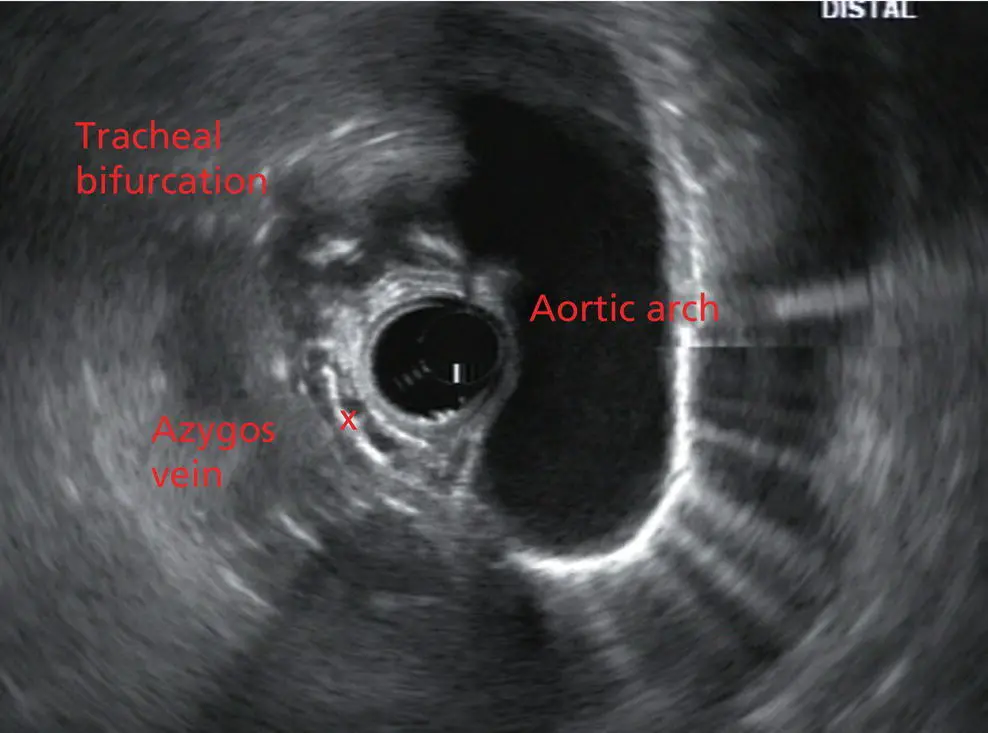

The endoscope can be pushed down from here or pulled up slightly from the position of the left atrium to reach the subcarinal space. Of interest in the subcarinal space are the right and left mainstem bronchi seen emanating out as ribbed‐like air‐filled structures. As many have suggested, these can be imagined to have the appearance of two headlights.

Figure 2.7 Radial array image at the mid aortic arch.

More proximally from the area at the AP window the aorta elongates and forms the aortic arch ( Figure 2.7). This usually creates a semicircle on the entire right side of the image correlating to the left‐sided arch. However, with usual orientation the aorta should not cross the midline. The left carotid and left subclavian artery can easily be seen to leave the aortic arch as small round structures on the right side of the image ( Figure 2.8). The brachiocephalic artery can sometimes be seen as well superior to the carotid on the right. As the scope is withdrawn the thyroid comes into view. For example, on the right of Figure 2.9a prominent thyroid can be seen with a cystic structure within it.